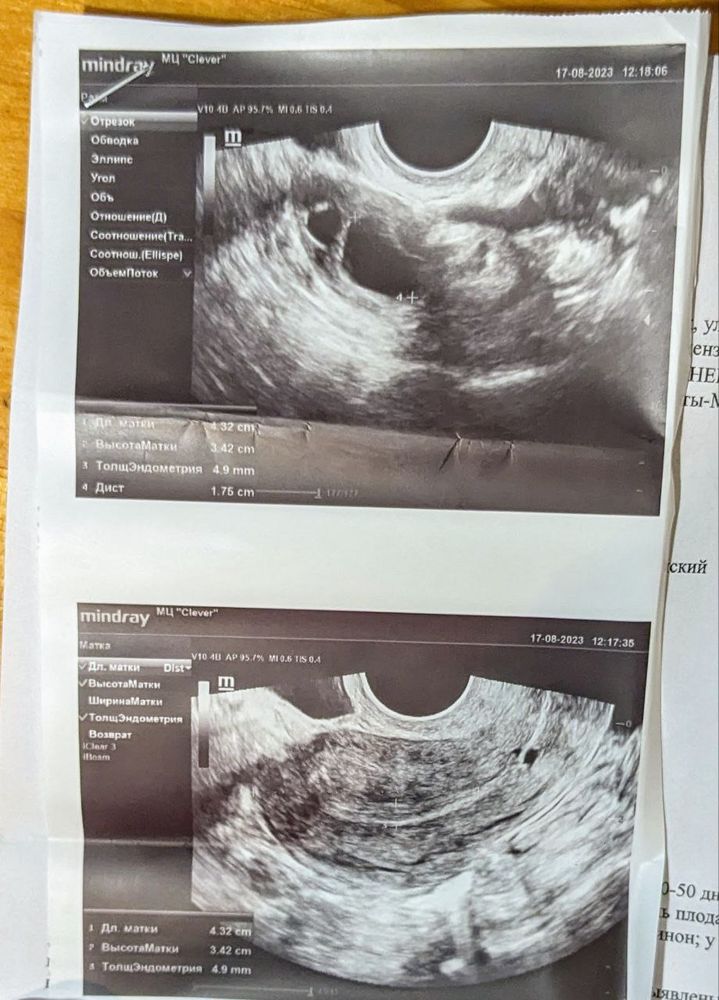

Врач была странной, сказала в левом яичнике ничего не вижу, ни фолликулов, ни ЖТ, в заключении написала, что в левом и правом фолликулы. Ничего не объяснила, не рассказала, отстраненной была и грубой видимо настроение «пришло» вместе с ней на работу. Я не в первый раз у этого доктора была, пол года у нее наблюдаюсь по планированию беременности. Такой прием был впервые, неясный и бесполезный я бы сказала. Я пойду на узи на днях еще и будет яснее, задам вопросы и т п. Но сейчас я мучаюсь вопросами и буду Рада услышать Ваши истории, опыт или что читали/слышали. Вопрос у меня такой, по поводу точек на снимке матки. Есть прошлые ухи и там матка, яичники и фолликулы абсолютно другие. Может ли это быть Б? …

Беременности скорее всего нет. По крайней мере в полости матки на узи плодного яйца нет(оно не так выглядит, как у вас там-это просто узи аппарат такие точки делает). Бывает такое, что в яичниках есть фолликулы, но нет именно доминантного, который потом овулирует. Судя по описанию у вас такое. Обычно желтое тело описывают на узи, если оно есть. Нет желтого тела-нет овуляции-нет беременности

Я фолликул вижу. А на какой день цикла вы делали? В общем, переделайте в другом месте.